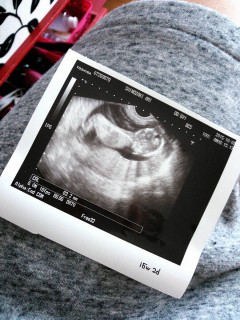

3日前から急に胎動感じなくなって、不安に思ってるより病院だ!って思って検診じゃないないけど行ったら、、、赤ちゃん元気でしたぁぁ=3 よかったぁぁ(´・ω・`) ちょっとでも不安に思った時はやっぱ病院行って解決した方が良いなって思った1日でした!!! 次の妊婦検診は3週間後(18w2d)次には性別分かるとイイナ~(´艸`) や~、ほんとよかっ!!